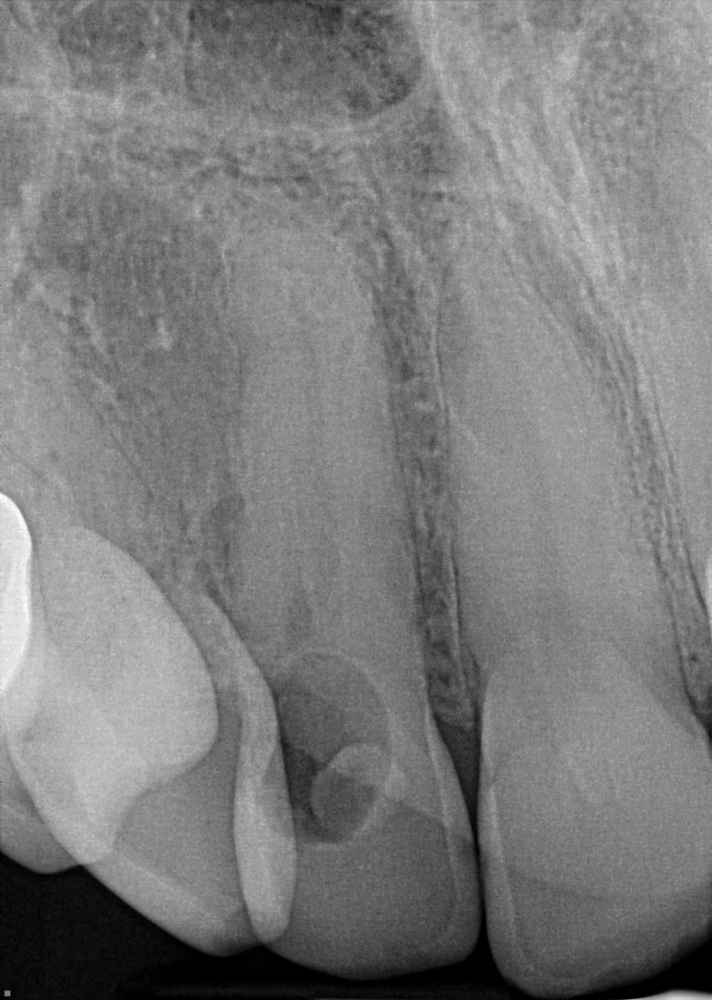

When using periapical radiographs in diagnosis, external resorptive defects should appear to move when captured from differing angulations and will have a visible and intact pulp chamber in all but advanced cases.1 All radiographic findings can help to differentiate ECR lesions from internal root resorption lesions, which have symmetrical, smooth, and clearly defined walls that appear to balloon out from the pulp chamber and do not appear to move with multiple parallax images. Conversely, ECR lesions have a less defined, irregular, and "ragged" or "moth-eaten" appearance and demonstrate variations in density, which makes them distinct from internal root resorption lesions that are usually uniform in density (Figure 7).2,14

On radiographs, early ECR lesions may exhibit a diminutive spot at the cementoenamel junction (CEJ), which may be confused with cervical burnout, but throughout the majority of the lesion, the root canal should be visible and intact. Advanced ECR lesions will appear as large radiolucent areas with less well-defined or "moth-eaten" borders that can extend into the pulp space.25 If an ECR lesion is in the repair-remodeling stage of development, it may appear more radiopaque due to the ossification of granulation tissue. Radiopaque spots may also be observed due to disruption of the PRRS that has led to local calcification of pulp tissue.6